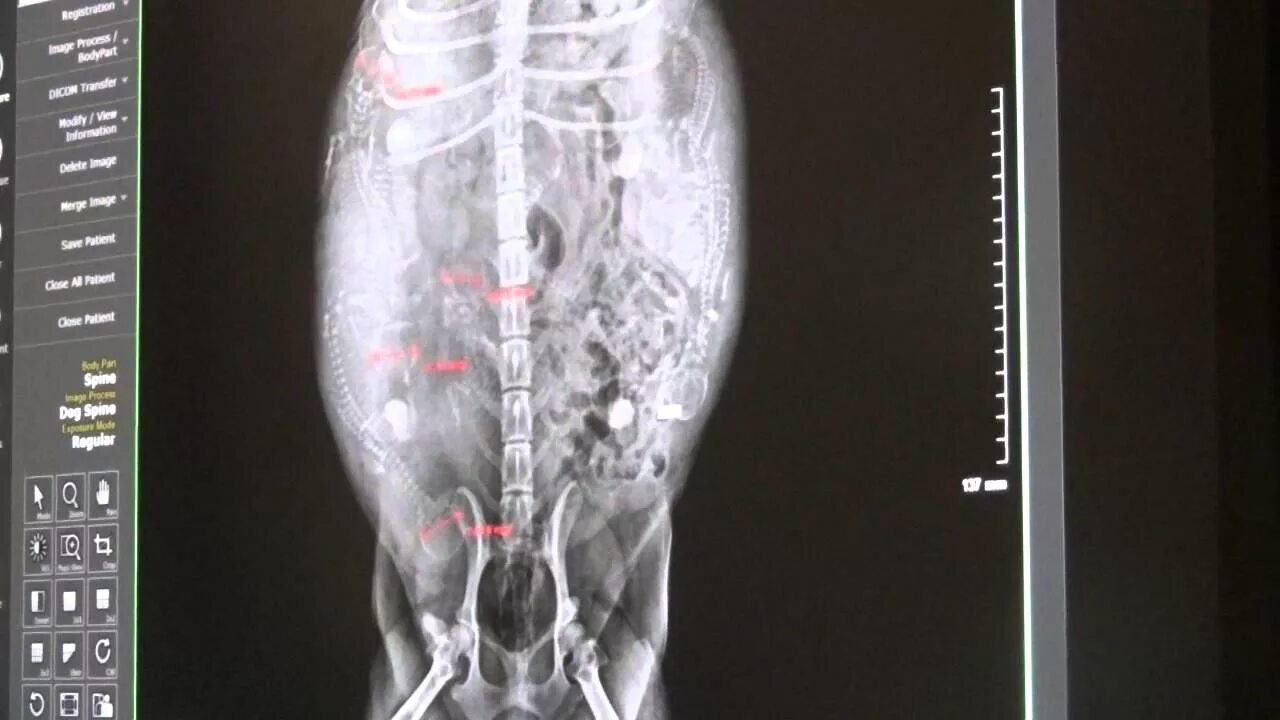

Делала рентген при беременности